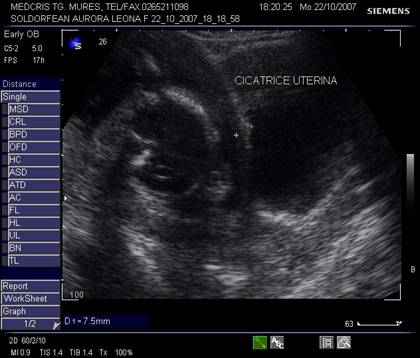

Fig. nr.233. Cicatrice uterina postoperatie cezariana ( cu hiperecogenitati , intre calipere ) pe segmentul unei sarcini de 24 sapt